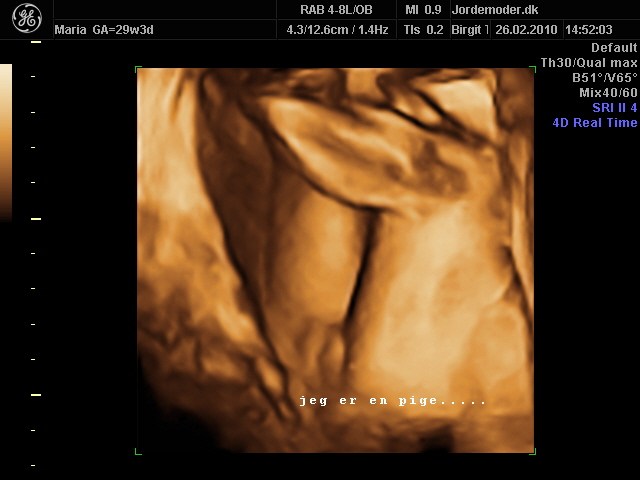

Først i 3D og så i 2 D..

Vedhæftede fotos (klik for at se i fuld størrelse)

Helt tydeligt, tak. En lille dreng . Synes også at det er meget nemmere på 3 D scanningerne. Du har ikke et fra 2 D vel?

Også helt tydeligt. Så tydelig er mit billede slet ikke selvom scanningsjordmoderen kunne se det efter 10 sek